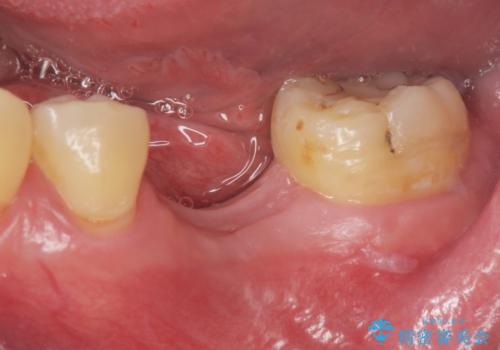

[ インプラント治療 ]失った奥歯を回復したい

![[ インプラント治療 ]失った奥歯を回復したいの症例 治療前](https://seimitsushinbi.jp/wp/wp-content/uploads/2021/11/036b501e44e72b51304eaa0dd62d1613-500x350.jpg?v=1637928855)